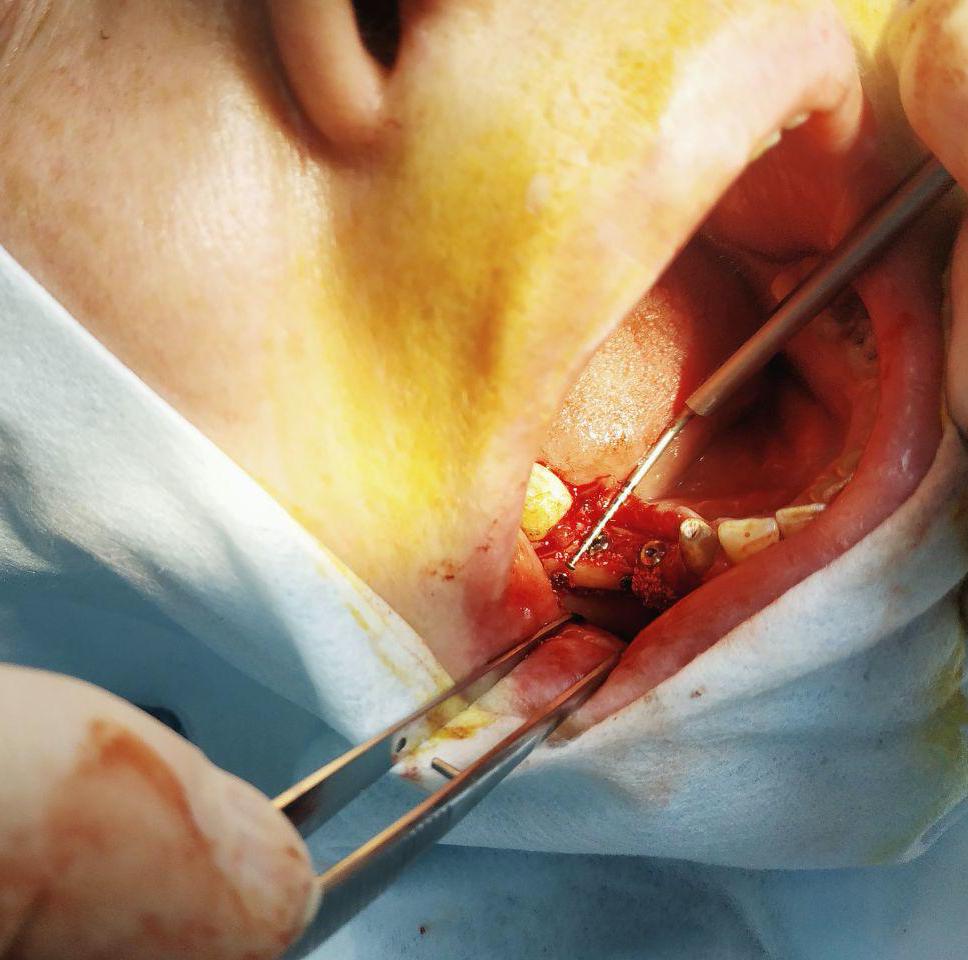

Лечение: Принято решение о пересадки ее собственной кости из угла челюсти. Отслоение слизисто-надкостничного лоскута. Забор блока кости в области угла челюсти. Остеопластика блоками + ксенографт. Установка двух имплантов. Наложение швов.